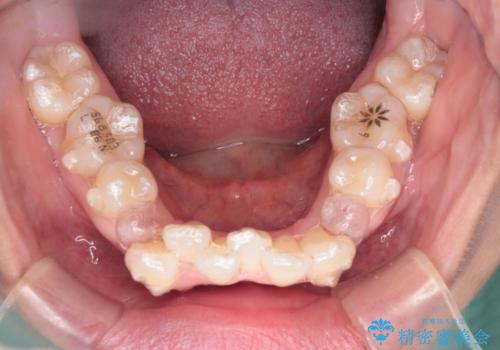

【抜歯ケース】前歯のガタガタをインビザラインで治療

- 前歯のガタガタを主訴に来院されました。

抜歯が必要なケースでしたが、インビザラインでの治療を希望されワイヤーを使用せずに治療を完了しております。